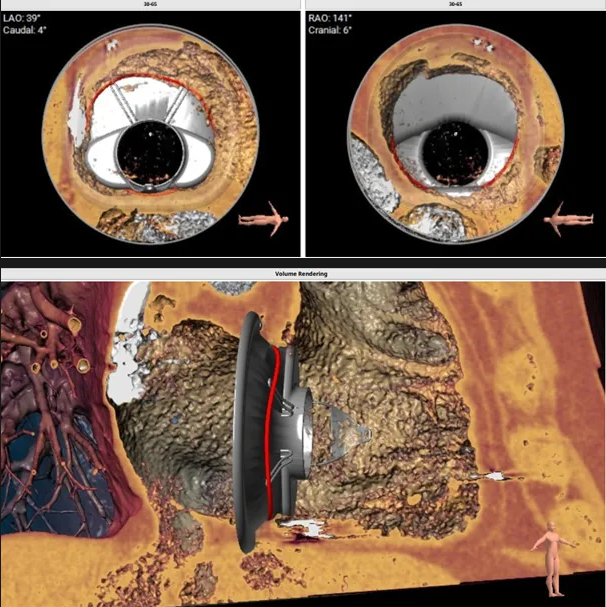

瓣膜植入模擬

術中經(jīng)食道超聲輔助下可見LuX-Valve Plus夾持件順利抓捕瓣葉,室間隔錨定位置良好,假體瓣膜整體錨定狀態(tài)穩(wěn)固。